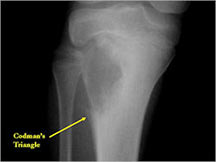

- May have Codman’s triangle and malignant appearing periosteal reaction in most cases

- Expands contour of bone and may appear similar to an ABC (aneurysmal bone cyst)